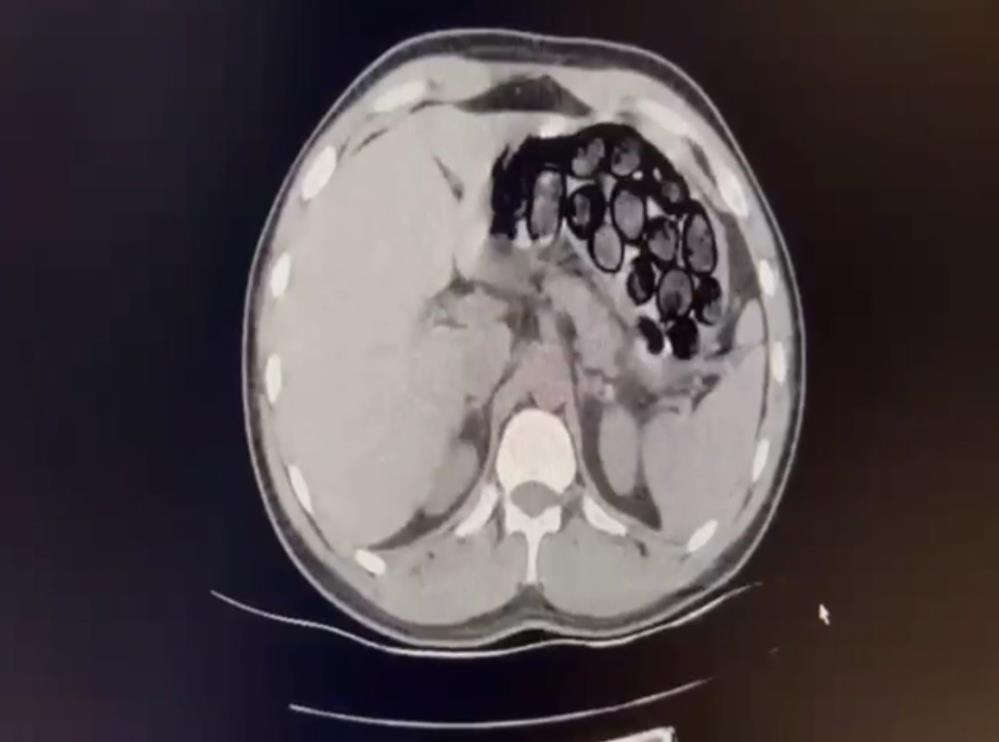

Jandarma ekiplerince takibe alınan İranlı şahıs ve beraberindeki 2 kişi, Kars’ın Selim ilçesi girişinde ticari takside yakalandı. Yapılan üst aramasında bir şey bulunamayan Omid Baghernezad, Kars Harakani Devlet Hastanesi'ne götürüldü. Burada çekilen röntgende Omid Baghernezad'ın mide ve bağırsağında kapsüller halinde 65 parça halinde 412 gram sentetik uyuşturucu olduğu belirlendi.